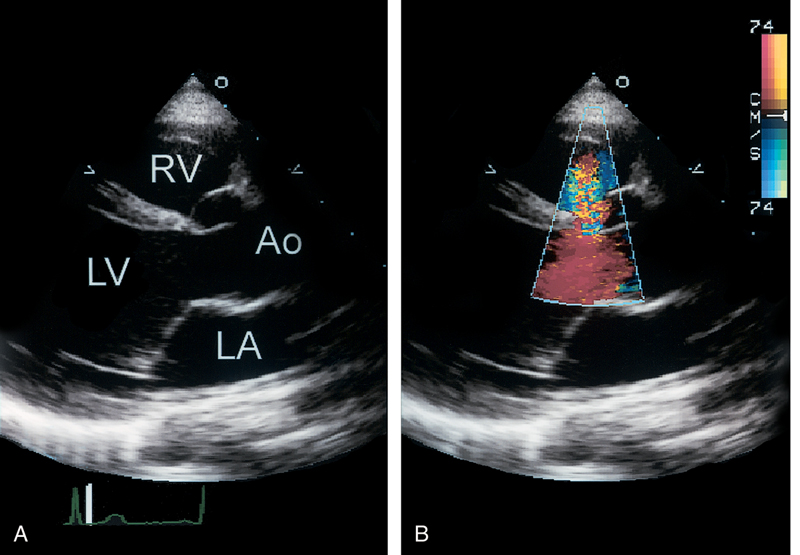

فحوصات تشخيصية لبعض امراض القلب والشرايين التاجية